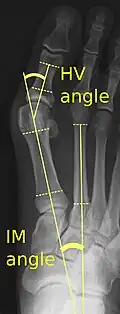

Bunions can be diagnosed and analyzed with a simple x-ray, which should be taken with the weight on the foot.[10] The hallux valgus angle (HVA) is the angle between the long axes of the proximal phalanx and the first metatarsal bone of the big toe. It is considered abnormal if greater than 15–18°.[11] The following HV angles can also be used to grade the severity of hallux valgus:[12]

- Mild: 15–20°

- Moderate: 21–39°

- Severe: ≥ 40°

The intermetatarsal angle (IMA) is the angle between the longitudinal axes of the first and second metatarsal bones, and is normally less than 9°.[11] The IM angle can also grade the severity of hallux valgus as:[12]

- Mild: 9–11°

- Moderate: 12–17°

- Severe: ≥ 18°